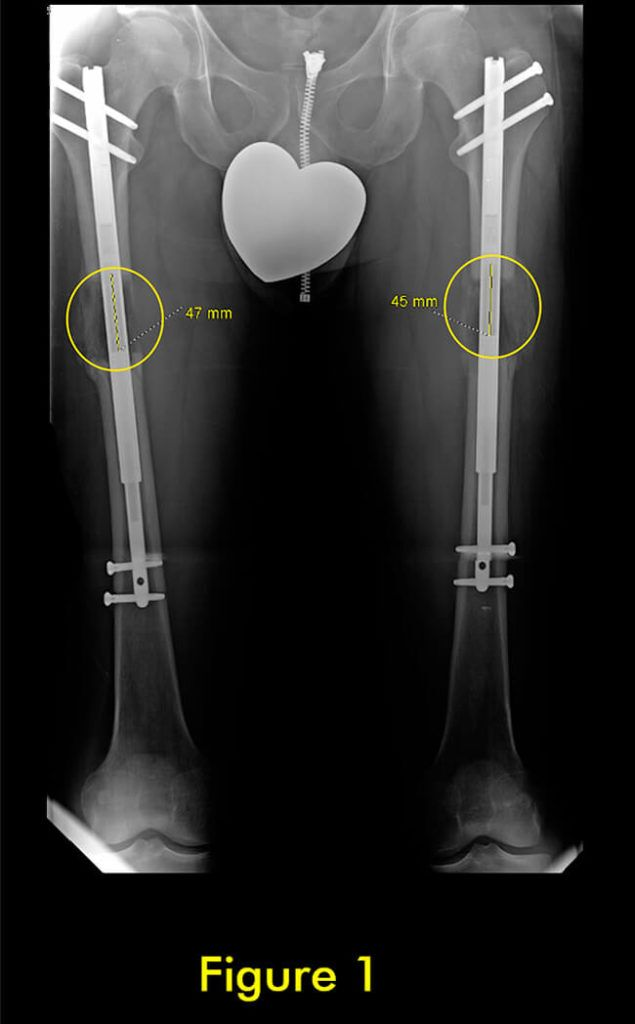

过早合并示意图1

图1:延长量细微差异

过早合并示意图2

图2:X光片确认诊断

过早合并示意图3

图3:重复截骨术

过早合并示意图4

图4:完全巩固